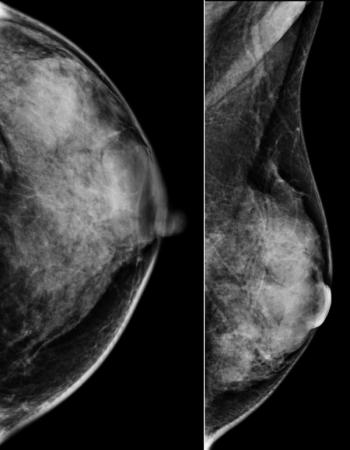

53-year-old BRCA2 positive patient presented for bilateral screening breast MRI.